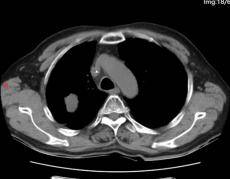

靶向治疗1个月后

所谓的精准武器,就是当时国内新获批的可医保报销的高选择性MET抑制剂。1月12日,69岁的老李开始口服这种靶向药物——MET抑制剂。仅仅28天,咳嗽、痰血和喘憋就明显减轻。复查CT,原本被肿瘤压瘪的右上肺重新张开,连支气管镜下的“菜花”样新生物也缩小了近一半。老李高兴地说:“睡觉不再被憋醒,走路也能跟上儿子了。”